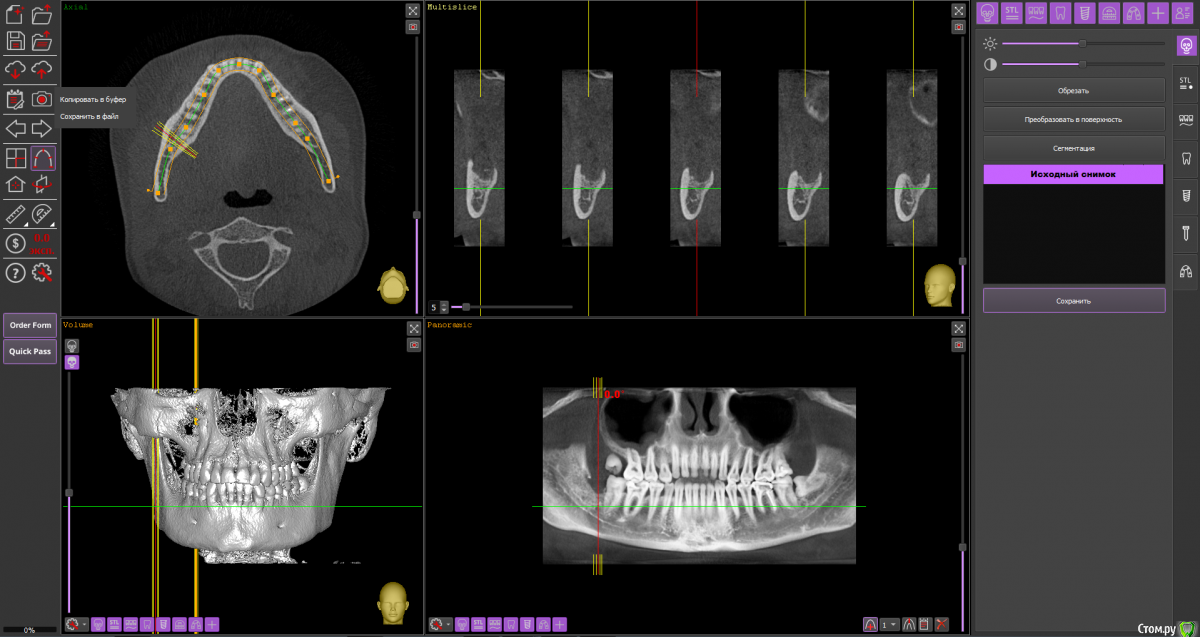

Спилка Опубликовано 15 октября, 2020 Поделиться Опубликовано 15 октября, 2020 В августе решилась на удаление нижних зубов мудрости (38 и 48). Врач - стоматолог-хирург посоветовала не удалять сразу оба, а по-очереди и начать с 48 зуба, ретинированного, дистопированного, возле которого больший очаг воспаления.В процессе удаления был сделан укол анестезии, потом разрезана десна, отпилена коронка зуба, упиравшаяся в соседнюю “семерку” - 47 зуб, и удалён корень, далее рана была зашита. В день операции прицельных снимков ни до, ни после не делали, врач руководствовалась КТ месячной давности, лунка после удаления не промывалась, лекарство, дренаж не ставились.Процесс удаления зуба прошел, на мой взгляд, быстро, дёргано, врач сразу же ушла после завершения, была не в настроении, явно чем-то обеспокоена. На свой счет я это не приняла, но осадок остался.Назначения врача в плане приема таблеток: нимесил, супрастин, амоксиклав, холод первые суткиАнтибиотик, в отличие от прочих назначений, был рекомендован при наличии болей на третий день после удаления.Меня предупредили, что операция сложная, “помучаюсь” с заживлением и восстановлением.Дома первые сутки прикладывала холод, пила нимесил и супрастин по нормам назначения.На третьи сутки супруг заметил, что изо рта стало “плохо пахнуть”, “гнилостно”, позвонил врачу, она сказала, что на третий день отёк самый большой, это норма, и посоветовала начать пить антибиотик, и если будет так же или лучше, все ок, если хуже - приехать на приём, лунку вскроют, заново сформируют сгусток и зашьют.На четвертые сутки после удаления ситуация ухудшилась, было принято решение показаться в областную клинику хирургу. В приемном отделении, увидев мою щеку, погоняли по кабинетам, взяли анализы, сделали рентген, КТ, ЭКГ, еще что-то - уже не помню, и …..поставили диагноз - флегмона околочелюстной области справа. И экстренно прооперировали. Подробности описывать не буду, жутко все это, никому не пожелаю... 11 дней в стационаре, выписали с открытой раной на амбулаторное лечение к хирургу по месту жительства.Я всю жизнь по стоматологам, много разных сменила, читаю информацию, что-то понимаю, но все же я не специалист. Эта клиника самая лучшая и дорогая в области, думала уж там все будет отлично. Но пока лечилась в областном стационаре, много читала и возникли сомнения, что удаление произведено отлично.После того, как рана затянулась, попытались прояснить этот вопрос с клиникой, где удаляли зуб. Там сказали, что я не добросовестный пациент, что никаких установленных нормативов, протоколов лечения не существует, соответственно, врач ничего не мог нарушить при проведении операции по удалению 48 зуба, попугали стоимостью экспертизы. И вообще, после вмешательства врачей областной клиники уже доказать ничего нельзя, засомневались в верности диагноза - флегмона околочелюстной области справа. По мнению директора клиники и глав врача удаление проведено идеально - они смотрели записи камеры наблюдения.Собственно - вопрос в чем - может они правы и удаление действительно прошло “идеально” - как они утверждают, и флегмоны не было.У меня есть 3Д снимки за месяц до удаления и через полтора месяца после. Как могла в программе выставила диапазоны, сделала снимки экрана. И кажется мне, что там осколки зуба в лунке… Муж сделал фото лунки - по-моему осколок видно.Я в растерянности, если клиника отработала идеально, почему такие катастрофические последствия?!! Если так можно - оцените ситуацию в целом, так как теряюсь сформулировать какой-то конкретный вопрос. Заранее спасибо всем! Ссылка на комментарий

Спилка Опубликовано 15 октября, 2020 Автор Поделиться Опубликовано 15 октября, 2020 Загрузите кт на файлообменникhttps://yadi.sk/d/cU-dxQlKtbsNfQКЛКТ И фото места где был зуб Ссылка на комментарий

Irouil Опубликовано 16 октября, 2020 Поделиться Опубликовано 16 октября, 2020 Вот именно мнение клиницистов меня и интересует, насколько правильно меня лечилиИменно это сказать клиницист не может в принципе, такие заключения даются на экспертизе врачом-экспертомКакой результат по вашему достигнут в стационаре, не подохла?Я бы выразился иначе, но суть Вы передали верно: главная цель лечения пациентов в экстренной медицине (а инфекционные воспалительные процессы, в первую очередь флегмоны, в челюстно-лицевой области являются показанием именно для применения такого вида лечения) - спасение жизни, ибо угроза для нее была. Теперь по существу Во-первых я не вижу на предоставленной компьютерной томограмме потенциально инфицированных фрагментов, угрожающих Вашему здоровью. И расскажите подробнее про губу - отмечается ее онемение? Сможете обрисовать карандашом область онемения и сделать фото? Ссылка на комментарий

Zlata-doctor Опубликовано 17 октября, 2020 Поделиться Опубликовано 17 октября, 2020 (изменено) Я не вижу никаких осколков на представленных снимках. Замечу, даже если бы они там и были, это не может являться причиной флегмоны. Патофизиология данного процесса гораздо более сложна и связана также с особенностями флоры вашей полости рта, вашего иммунитета, с непростой анатомией данной области, сложностью удаления и другими факторами. И таки да, околочелюстной области как анатомического образования, не существует. Промывание, введение лексредств и дренирование проводятся врачом по показаниям, он не должен 100% это сделать, а иногда это и нежелательно. Также хочу Вам сказать, что здесь собрались врачи, которые абсолютно бесплатно в рамках своей компетенции пытаются помогать вам, пациентам. И никакая это не цеховая солидарность, просто проводить экспертизу и ставить вердикт на расстоянии, не имея полной задокументированной истории вашей болезни-непрофессионально, преступно и аморально. К сожалению, люди сейчас воспитаны на скандальных ТВ роликах, где диагнозы обвинения, а заодно и приговор раздаются на раз-два. Здесь такого горлопанства в погоне за сенсацией не будет. Мы вам очень сочувствуем и желаем скорейшего выздоровления. Изменено 17 октября, 2020 пользователем Zlata-doctor 5 Ссылка на комментарий